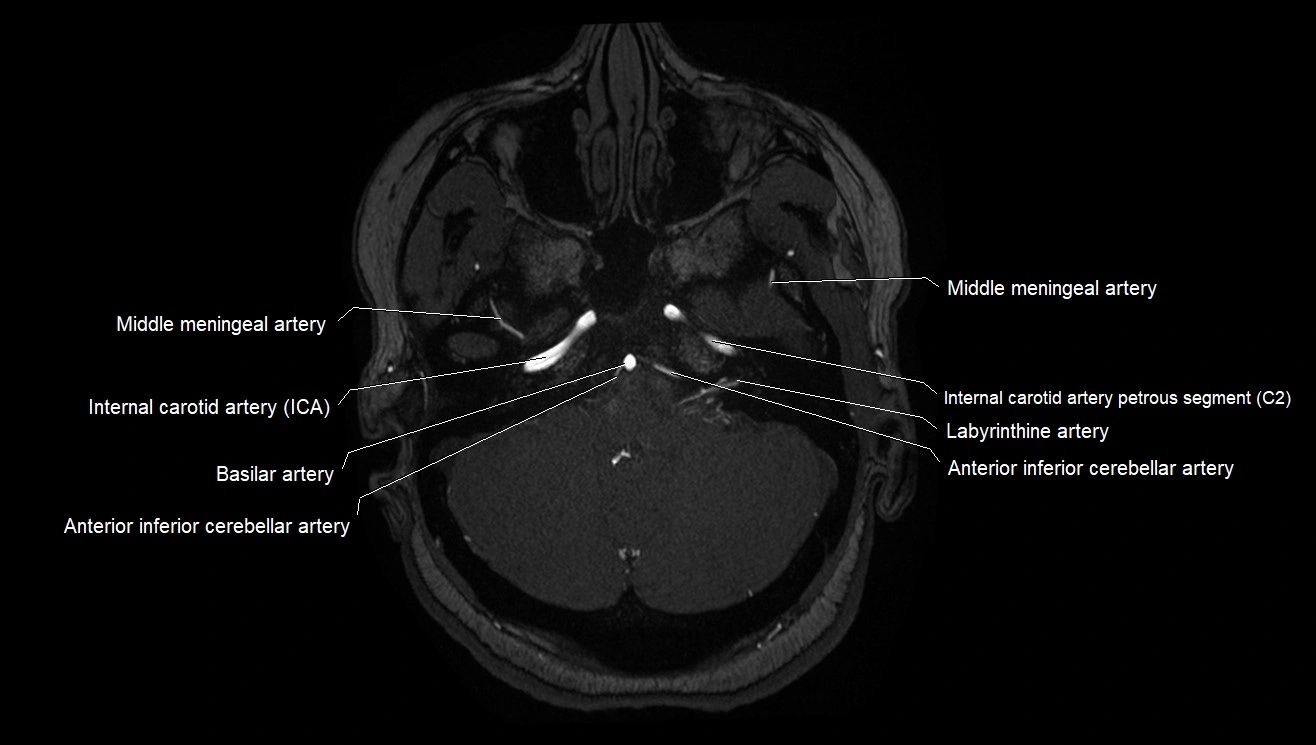

MRA (Magnetic Resonance Angiography):

• Flow-related enhancement makes the AChA appear as a bright, linear vascular signal against suppressed background

• High sensitivity for origin and proximal course; distal branches may be too small to resolve

• Detects stenosis, occlusion, aneurysm, AVM feeders

CT images

image